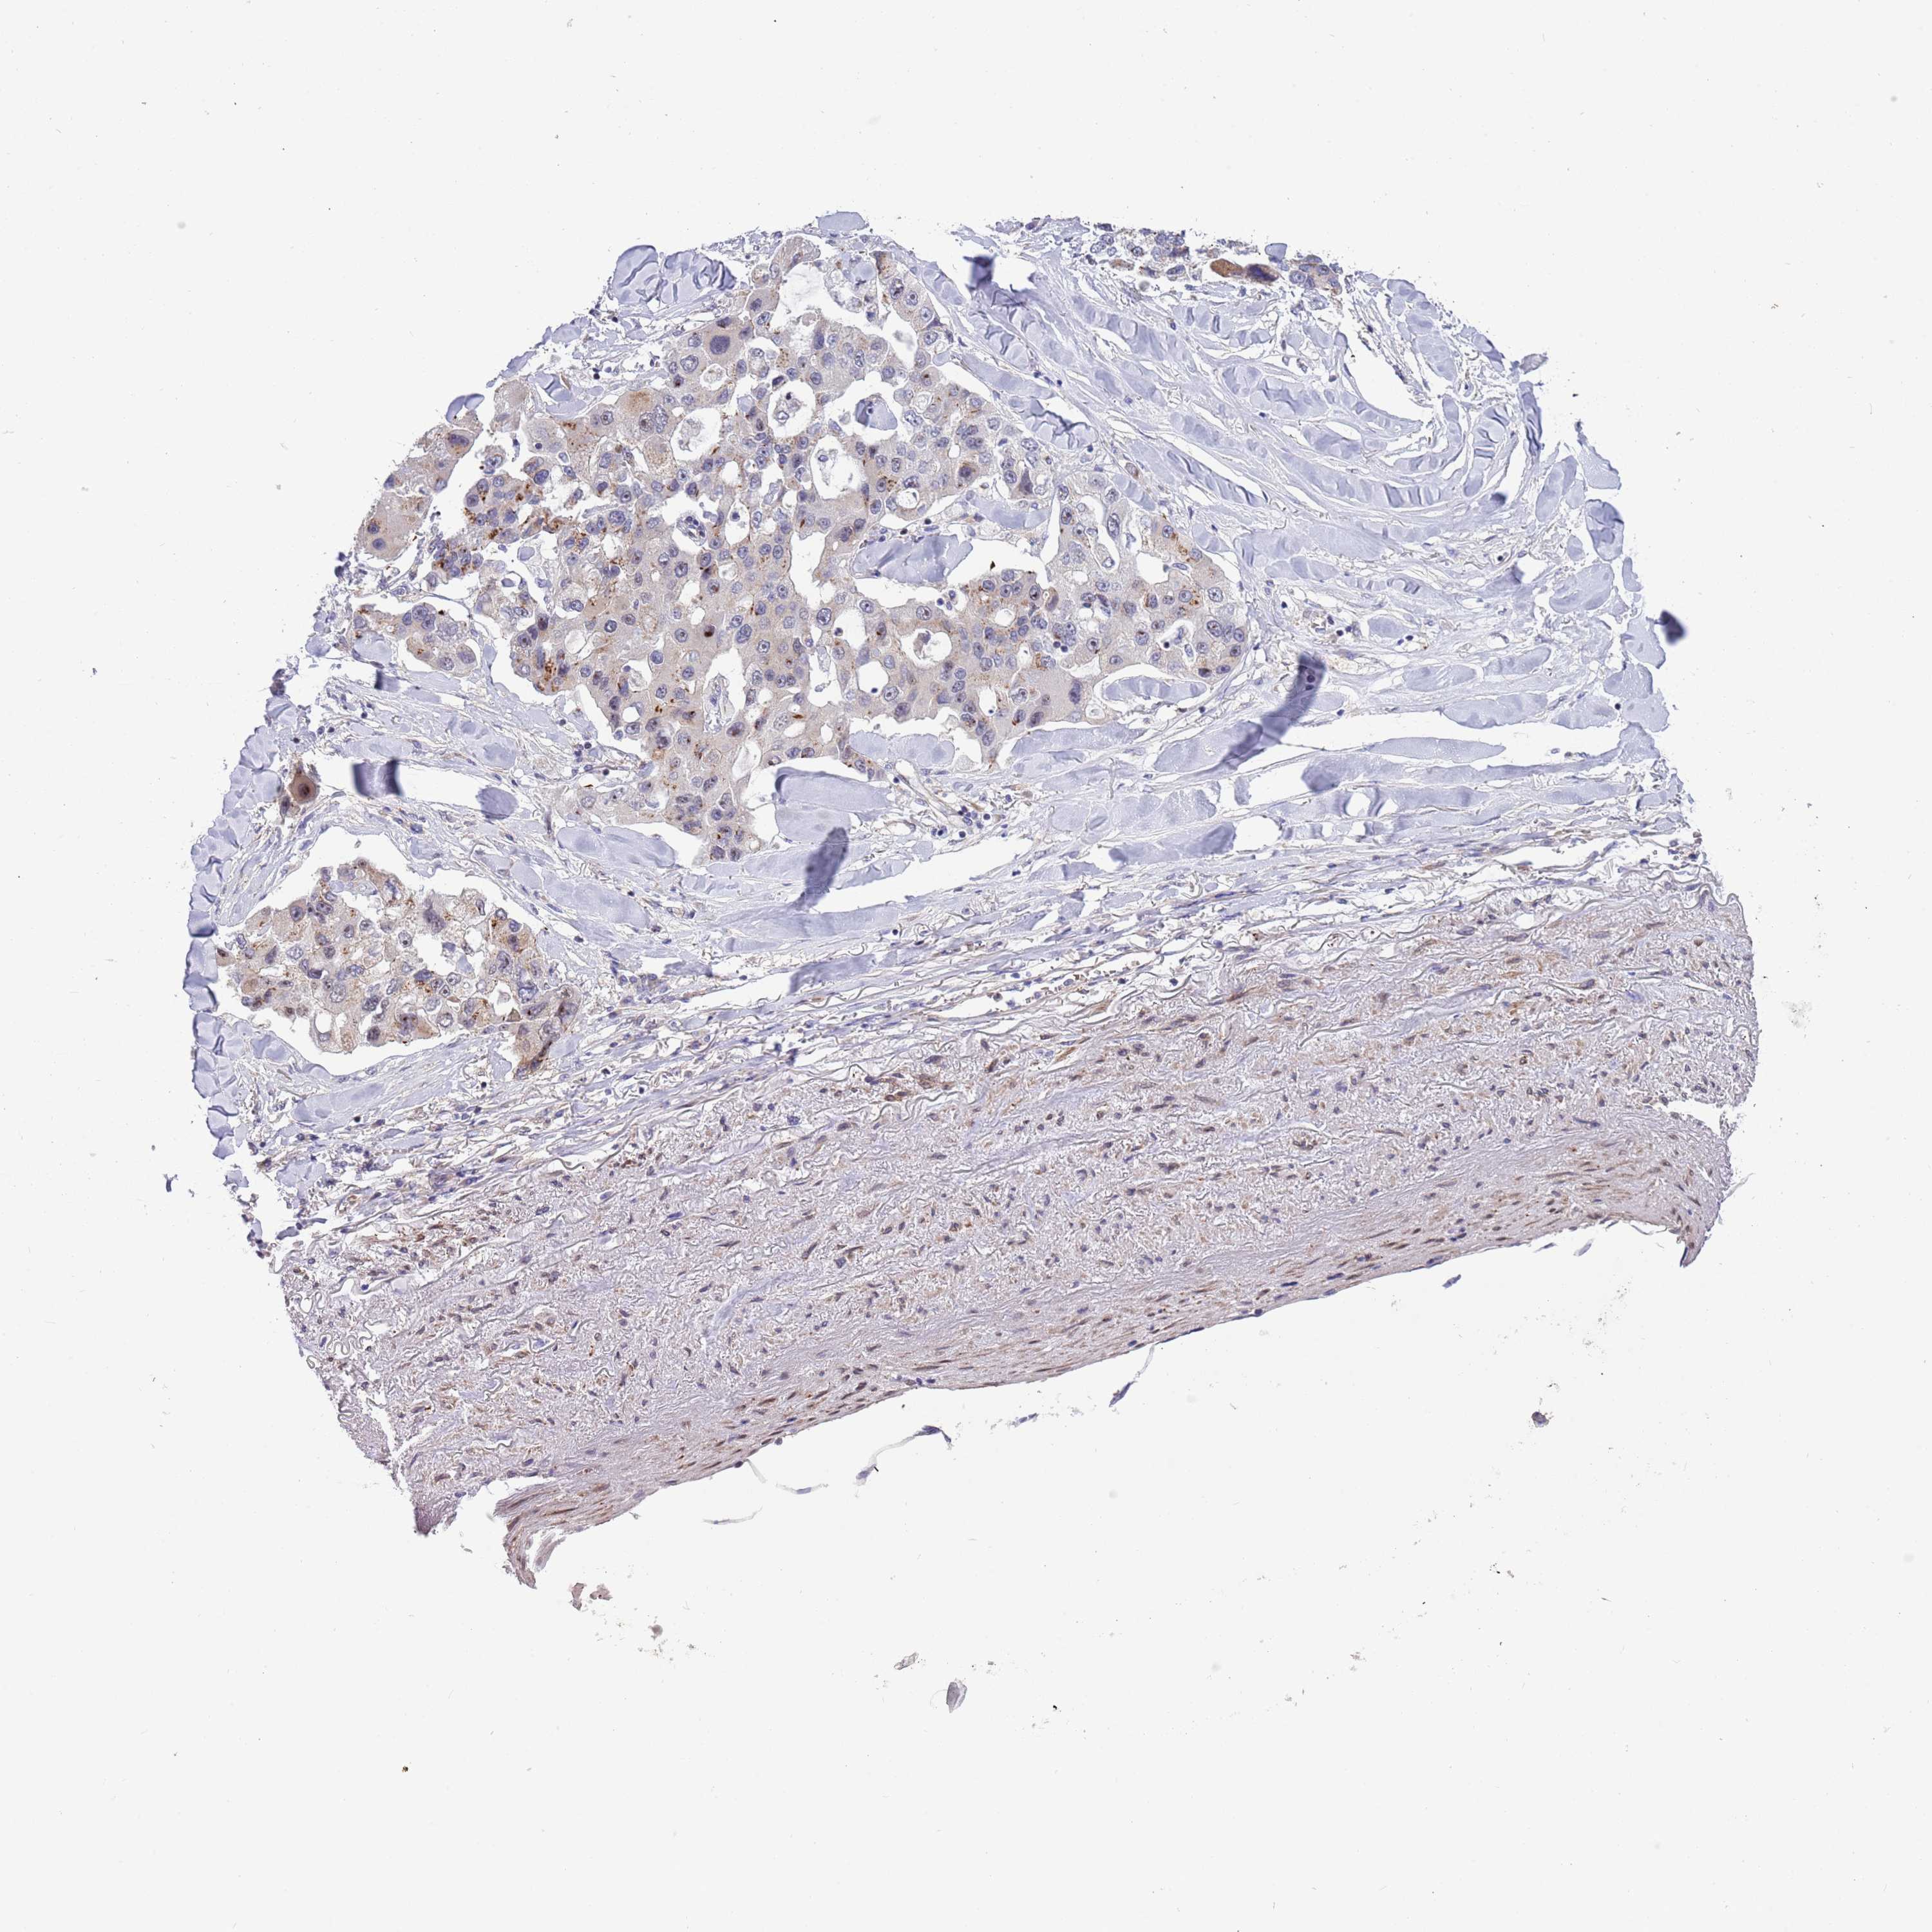

CANCER LUNG CANCER Show tissue menu

Lung cancer

Human cancer

Lung adenocarcinoma

Lung squamous cell carcinoma